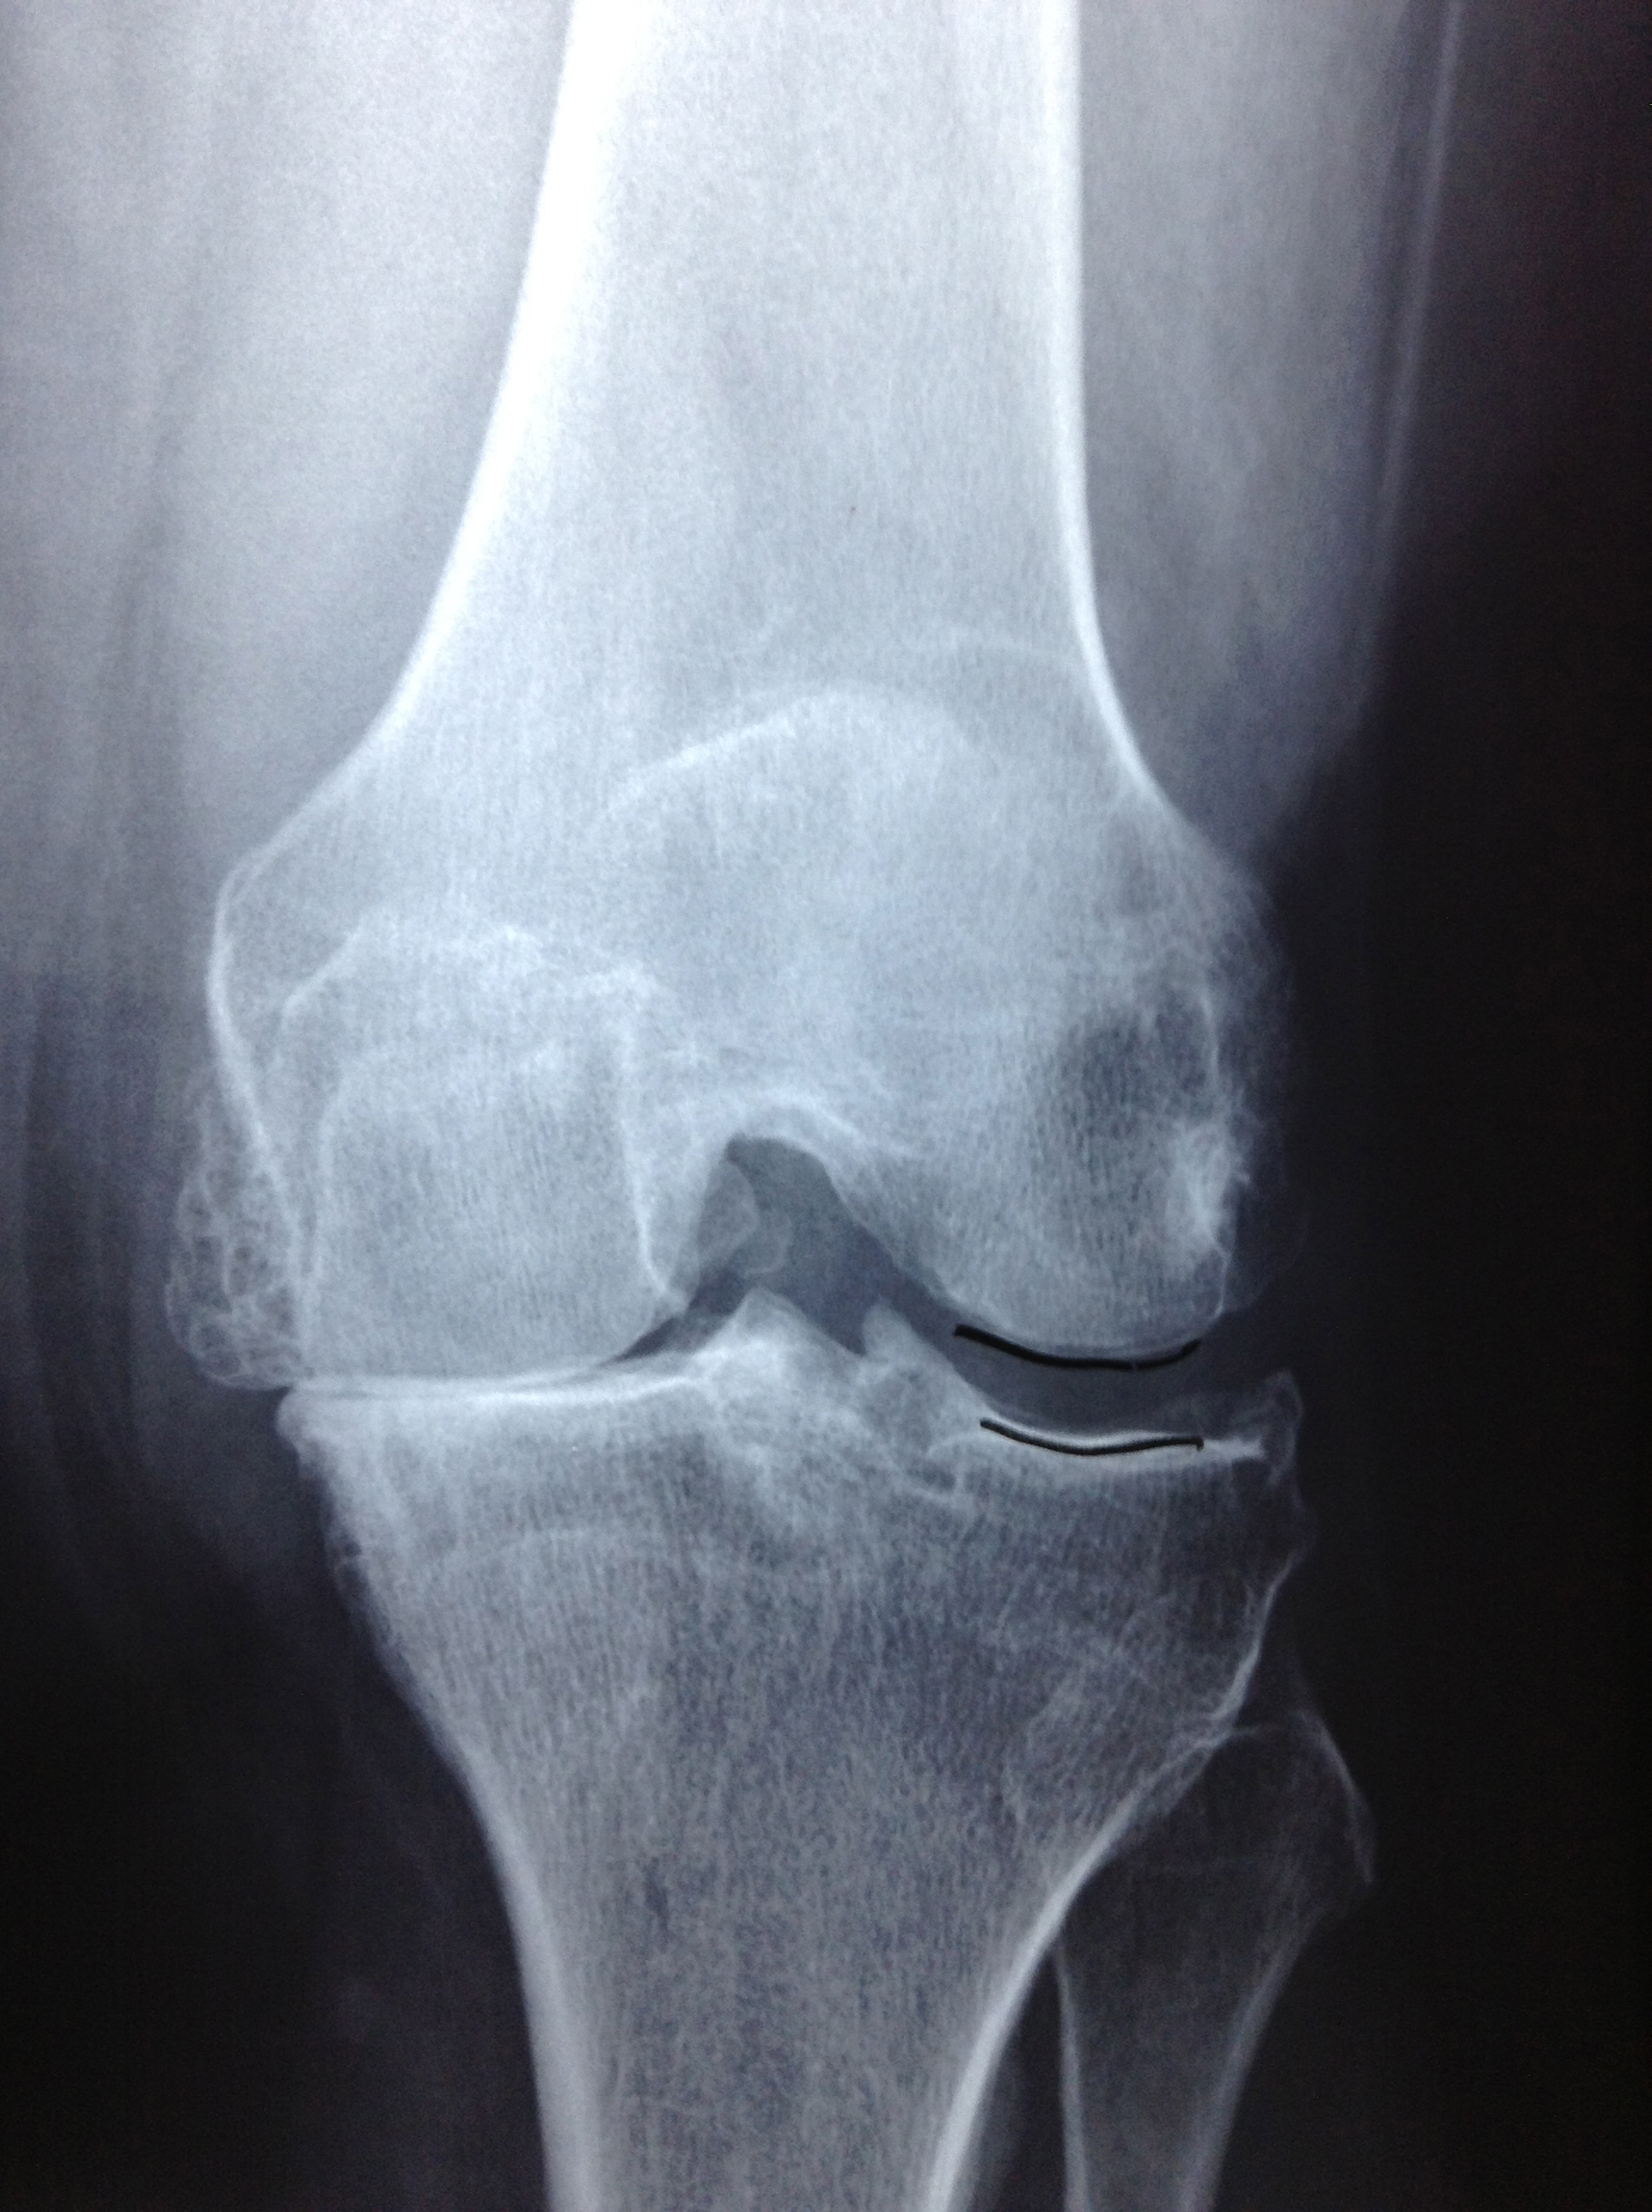

Revision Total Knee Replacement After Infection

• Revision Total Knee Replacement After Infection